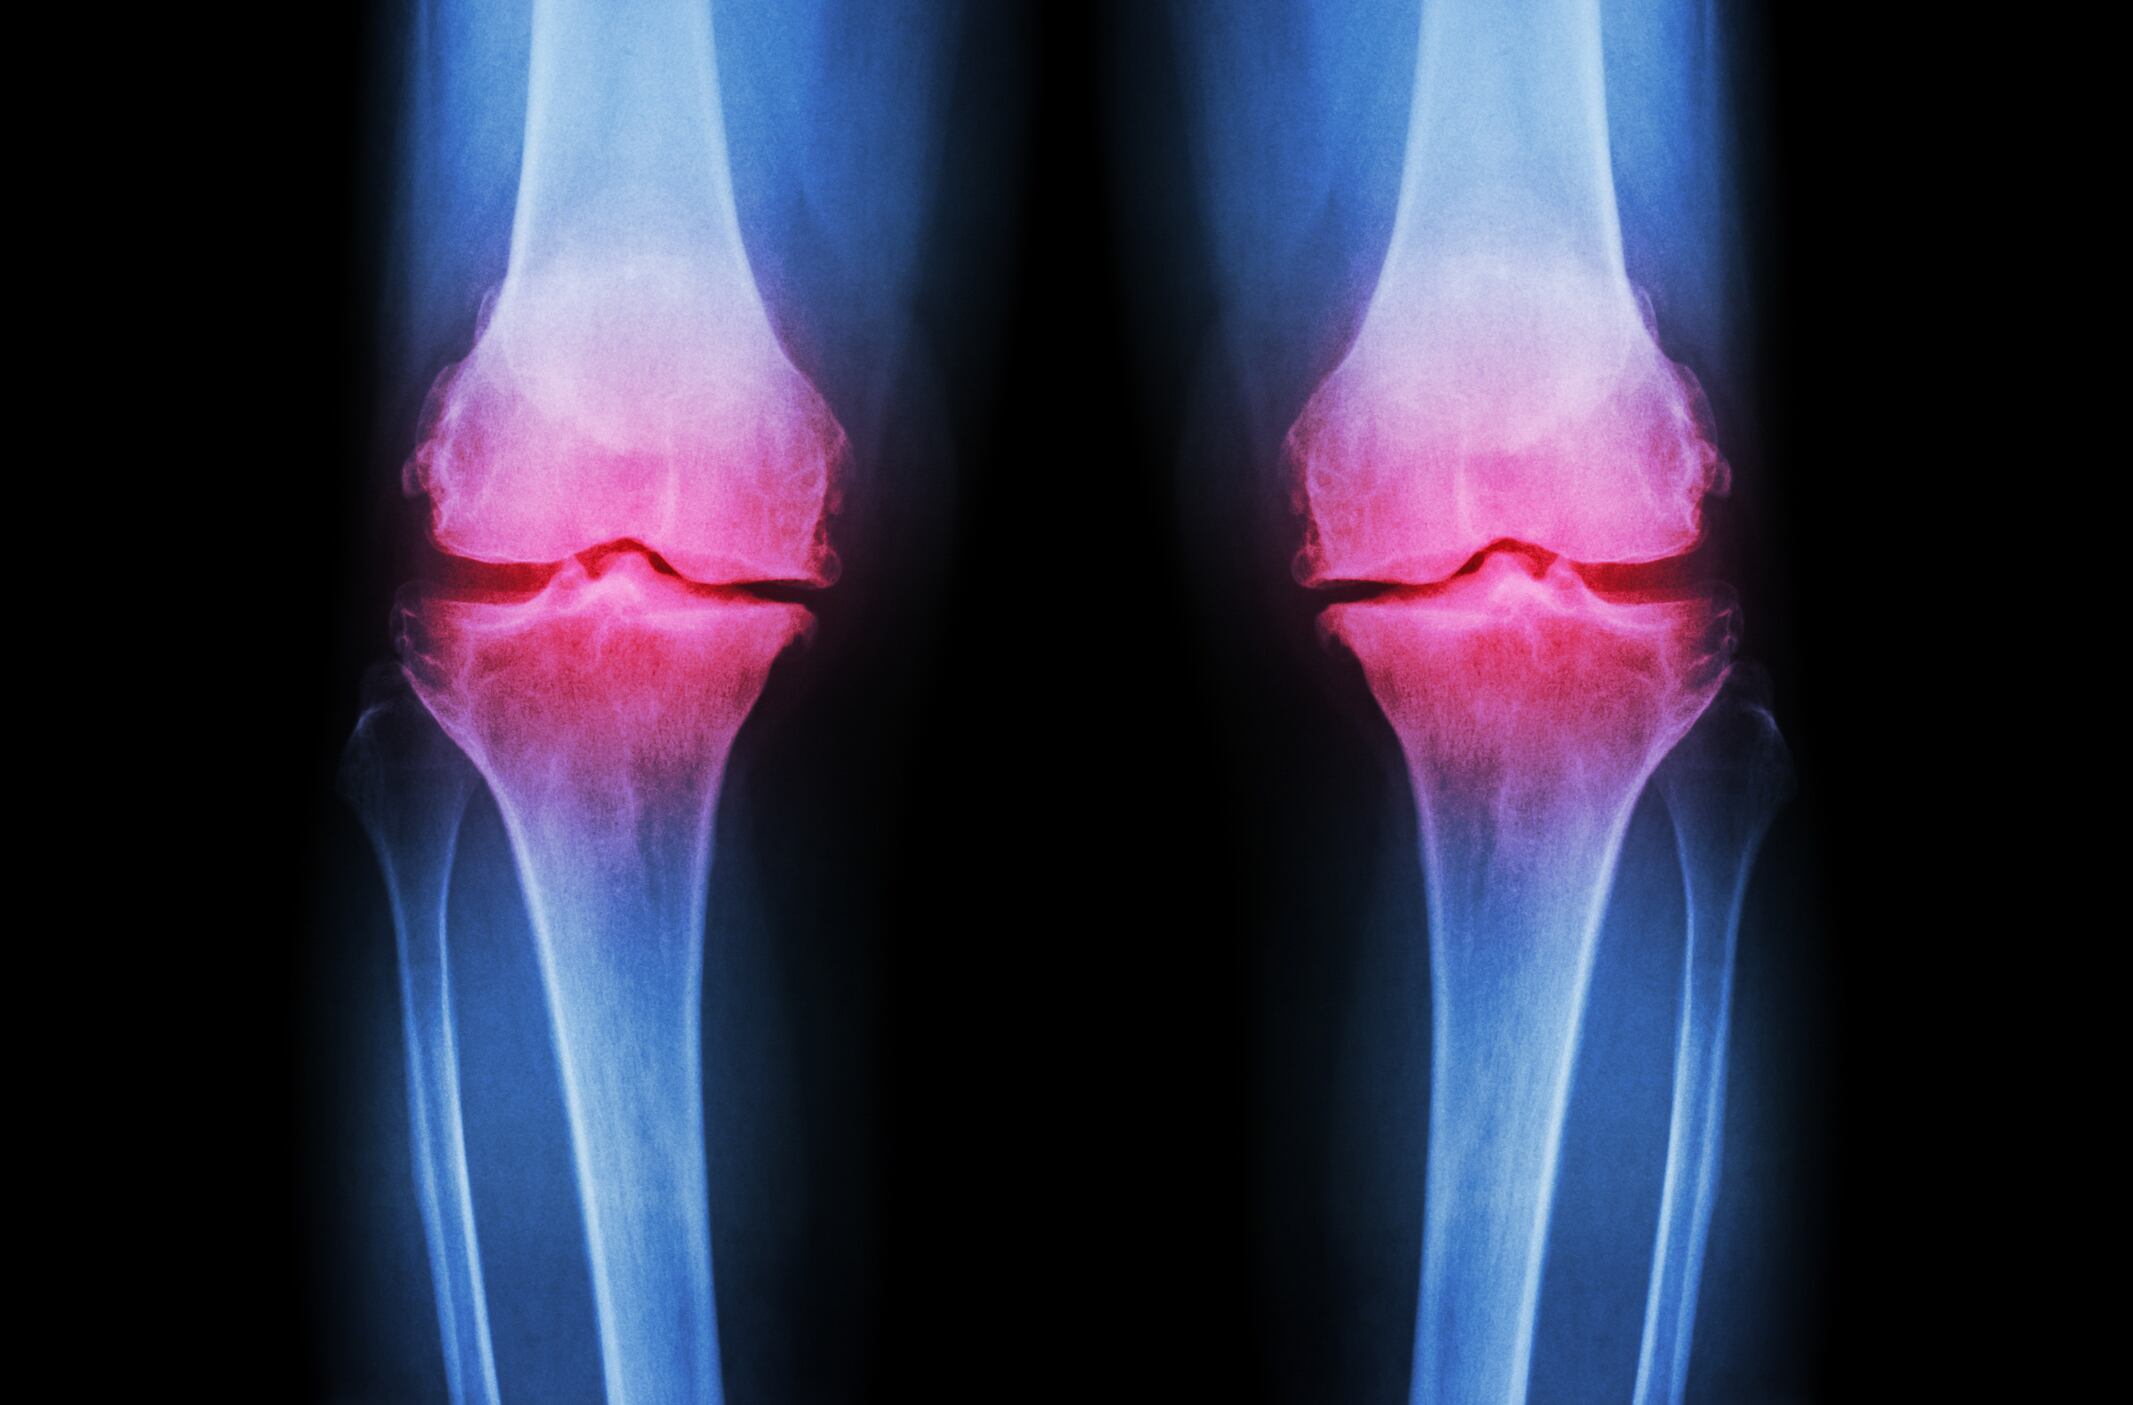

Performed in people suffering from mild to moderate knee osteoarthritis (OA), the new study indicated that 300 mg per day or 600 mg per day doses of the extract (HP Ingredients’ ParActin) led to significant reductions in pain, stiffness, and function, according to the Western Ontario and McMaster Universities Osteoarthritis Index (WOMAC)

The researchers, led by HP Ingredients’ Juan Hancke, PhD, recruited 103 adults with mild to moderate knee osteoarthritis to participate in their double‐blind, randomized, placebo‐controlled study. Participants were randomly assigned to receive 300 or 600 mg daily of ParActin, or placebo for eight weeks.

Results showed that people in both ParActin groups experienced a significant and progressive reduction in WOMAC pain starting at day 28 of the study.

In addition, WOMAC stiffness scores, physical function score, and the fatigue score all showed a significant improvements in both ParActin groups, compared to placebo.